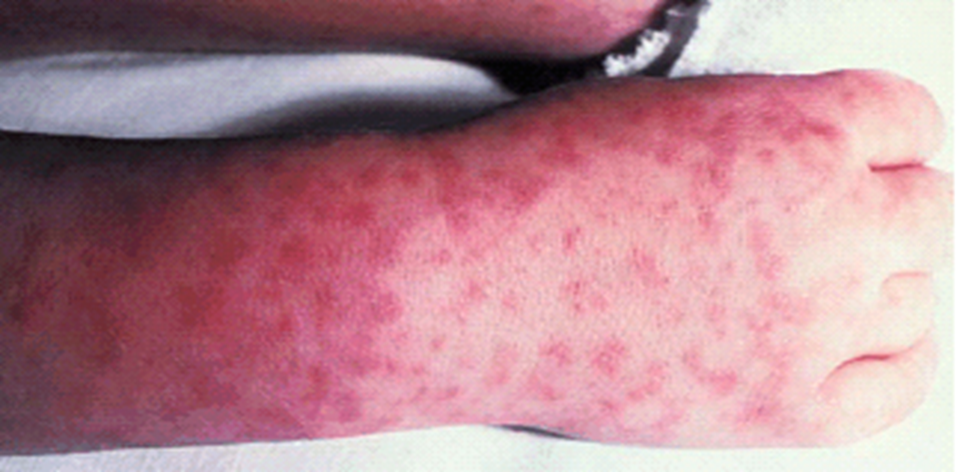

| მაკულოპაპულური/პეტექიური იწყება კოჭებსა და მაჯებზე | კლდოვანი მთების ლაქოვანი ცხელება |

● კანის გამოკვლევა – დერმატოლოგიური მონაცემები შეიძლება მიუთითებდეს კონკრეტულ ეტიოლოგიაზე (ცხრილი 7).

მაგალითად:

• ვეზიკულური გამონაყარი ახალშობილებში, რომლებსაც აქვთ ცნს-ის ჰერპეს სიმპლექსის ვირუსი (HSV) (სურათი 1A-C).

(სურათი 1A-C).

ახალშობილის თავის კანის დაზიანება, რომელსაც აღენიშნებოდათ კანის, თვალის და პირის ღრუს ახალშობილთა ჰერპესული ვირუსული ინფექცია, რომელიც დაკავშირებული იყო ნაყოფის თავის კანთან. გრამის წესით შეღებილი ნაცხი და ბაქტერიული კულტურები უარყოფითი იყო და დაზიანებები არ რეაგირებდა ადგილობრივ და სისტემურ ანტიბიოტიკებზე. ვირუსულ კულტურებში გაიზარდა მე-2 ტიპის ჰერპესული ვირუსი და დაზიანებებმა მოახდინა რეაგირება ინტრავენურ აციკლოვირზე.

• კლდოვანი მთების ლაქოვანი ცხელების გამონაყარი (სურათი 4), რომელიც, როგორც წესი, არ ვლინდება ცხელების დაწყებიდან რამდენიმე დღის განმავლობაში.

(სურათი 4)

კლდოვანი მთების ლაქოვანი ცხელების მქონე ბავშვს აქვს დამახასიათებელი გამონაყარი, რომელიც, როგორც წესი, ცხელების დაწყებიდან რამდენიმე დღემდე არ ჩნდება.